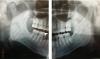

У моего мужа в возрасте 17 лет был удален нижний передний зуб, сейчас ему 28, прошу совета у специалистов, надо ли зубы сдвинуть, чтобы закрыть щель, или раздвигать, чтобы поставить искусственный зуб?